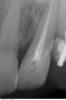

SergioS Опубликовано 27 апреля, 2013 Поделиться Опубликовано 27 апреля, 2013 Уважаемые коллеги, подскажите как бы кто поступил в данной ситуации:21 наружняя резорбция, в канале цемент, при попытке ревизии выскочили в резорбцию, инструмент заклинил и остался. В канале Vitapex, последние 2 мм не пройдены.У нас варианта 2:1.Пломбировка альфа-гуттой, хирургическим путем извлечь инструмент, MTA, остеопластический материал и под наблюдение.2..Пломбировка альфа-гуттой, резекция,MTA, остеопластический материал и под наблюдение.Снимки. Ссылка на комментарий

SergioS Опубликовано 28 апреля, 2013 Автор Поделиться Опубликовано 28 апреля, 2013 Изначальная ситуация на первом снимке. Так пациент пришел из гос клиники. В каналах цемент. Ссылка на комментарий